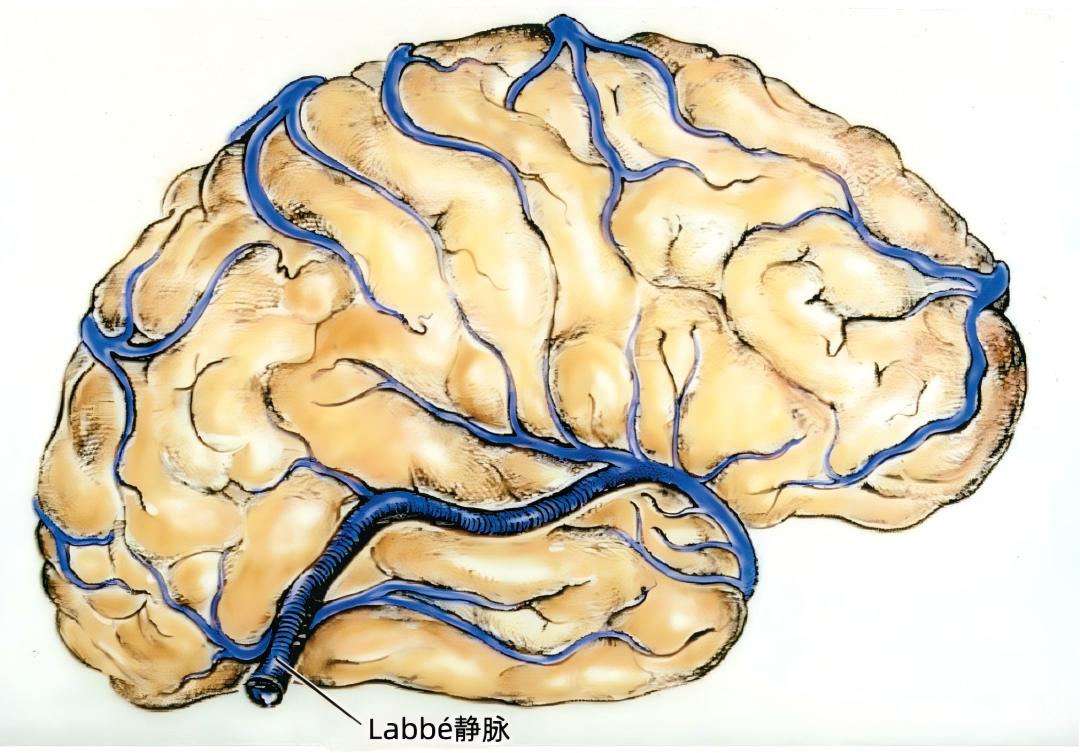

▼2.Labbé静脉

Labbé静脉也称下吻合静脉,是跨越颞叶外侧,连接外侧裂与横窦之间的最大吻合静脉。它通常起自外侧裂中部,行向后下,进入横窦前部。 Labbé静脉经过颞叶表面的位置有可能非常靠后甚至位于颞叶的最后界,或非常靠前达颞叶前1/3的外侧面。在此研究的20例半球中,12例Labbé静脉位于颞中静脉水平,6例位于颞后静脉水平,2例位于颞前静脉水平。有时会有两条Labbé静脉,其中后支通常会粗大一些。

下图示右颞叶和外侧裂。外侧裂浅静脉的前部细小,而汇入Labbé的后部粗大。一支颞中静脉沿颞上沟形成一桥静脉,跨过半球下缘汇入小脑幕窦。外侧裂浅静脉还通过两条Trolard静脉与上矢状窦吻合:一条经过额叶,另一条经过顶叶。颞外侧裂静脉引流颞上回,汇入外侧裂浅静脉和颞中静脉。

下图示横窦和小脑幕窦的分支。抬起颞叶的后部,暴露进入横窦的Labbé静脉、颞后静脉和枕后静脉,从颞叶底面进入小脑幕窦的颞底静脉。

下图示放大观。从前方暴露Labbé静脉。从后部颞下入路手术,可能牺牲Labbé静脉和来自颞叶、枕叶外侧面的静脉,还可能需要牺牲多条汇入小脑幕窦的颞底静脉和枕底静脉。

下图示小脑幕的上面观。右侧Labbé静脉和颞后静脉直接引流入横窦。

小脑幕组(上图 绿色)的桥静脉汇入行经小脑幕的静脉窦,即小脑幕窦或小脑幕附近的横窦和岩上窦。本组静脉引流颞叶外侧面和底面、枕叶的底面,包括颞底静脉、枕底静脉和来自颞叶外侧面的降静脉,如Labbé静脉。 除Labbé静脉外,这些静脉虽然有可能进入横窦,但大多数围绕半球的下缘汇聚于枕前切迹到达外侧小脑幕窦。而Labbé静脉通常汇入横窦。大脑底面的桥静脉汇入静脉窦之前,经常粘连于与中颅窝底硬膜和小脑幕表面。 从外侧面引流入小脑幕窦的静脉包括颞前静脉、颞中静脉、颞后静脉和Labbé静脉。

在颞底的后方可能遇到许多桥静脉(下图),这些静脉包括颞、枕、颞底、枕底静脉和Labbé静脉,伤及这些从大脑半球下表面进入横窦和小脑幕窦的静脉,经常会产生某种程度的静脉梗塞和颞叶水肿。这些静脉闭塞以后,有可能导致对侧肢体偏瘫,其中面部和上肢较下肢更明显,优势半球受累还可能导致失语。 在横窦和岩上窦结合部抬起颞叶时经常遇见的难题是有许多来源于颞叶外侧面和底面的静脉聚集在这一区域(上图)。颞下入路手术后遗症的产生往往是因为Labbé静脉的闭塞;但是术中单纯烧闭Labbé静脉的情况并不多,因为当颞下入路需要在颞叶内侧暴露小脑幕缘时,也需要牺牲其他许多这一区域的桥静脉。